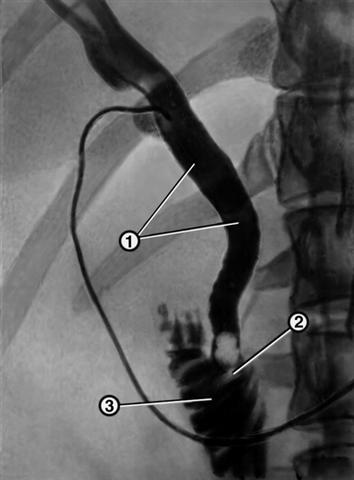

Рис. 2. Рентгенограмма, полученная при интраоперационной холангиографии у больного желчнокаменной болезнью: общий желчный проток (1), в который введен катетер, расширен в его дистальной части определяются камни (2), рентгеноконтрастное вещество выходит в двенадцатиперстную кишку (3).